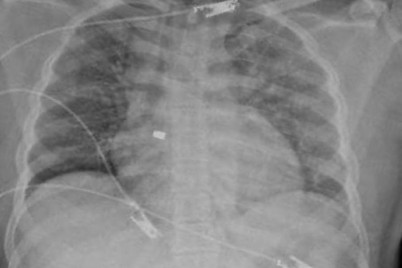

تمكن فريق مسار الإصابات بتجمع الرياض الصحي الأول من إنقاذ حياة مقيم؛ أصيب بطلقة نارية في منطقة الصدر. وفي...